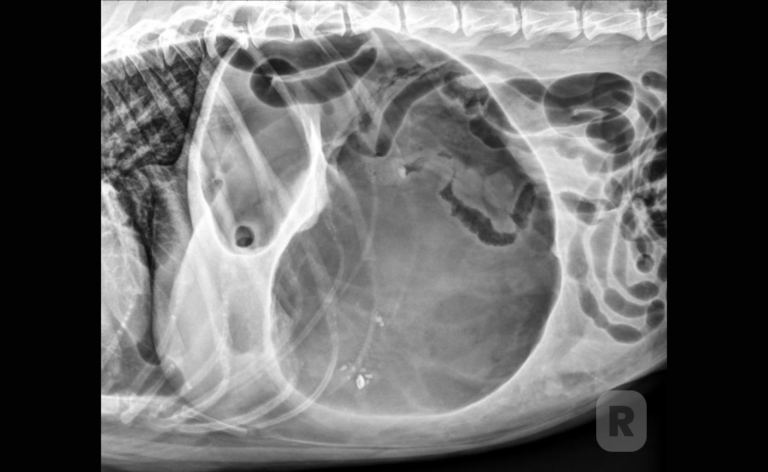

Gastric Dilatation-Volvulus Syndrome in Dogs

In this Vetpocket™ article, Dr. Shadi Ireifej provides essential pathophysiology, risk factors, breed predispositions, radiography, surgical approaches, surgical survival rates, and more for gastric dilatation-volvulus